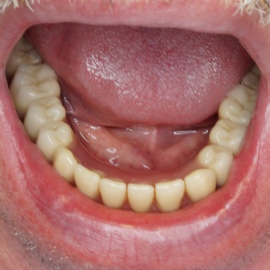

• Implanty jako zakotwiczenie protezy częściowej i całkowitej

Nie u każdego pacjenta można wykonać stałe odbudowy protetyczne oparte na implantach. Powody najczęściej sa prozaiczne, takie jak koszty, niekorzystne początkowe warunki kostne i wymagane rozległe odbudowy kości, strach przed bólem a także - jakże często - zdrowy rozsądek. Wiadomo bowiem, że w przypadku rozległych, trudnych technicznie do wykonania regeneracji kostnych zwiększa się obciążenie organizmu, oraz możliwości wystąpienia powikłań, a więc zwiększa się ryzyko niepowodzenia w leczeniu. Dlatego wykorzystujemy implanty jako zakotwiczenie atachmentów do utrzymania protezy ruchomej. Takie rozwiązanie pozwala na zmniejszenie kosztów, ograniczenie zakresu zabiegu, oraz co najważniejsze pozwala na poprawę jakości życia i zadowolenia z użytkowania protez ruchomych.

Pacjentka głosiła sie do naszego gabinetu do leczenia z osadzonym mikroimplantem w pozycji lewej dolnej dwójki. Siostrzany implant w pozycji prawej dolnej dwójki wypadł wcześniej, około 1,5 roku od implantacji. Odtworzono przedsionek i dziąsło rogowaciejące, osadzono dwa implanty, jednoczasowo z regeneracją kości. Dopiero na etapie ostatecznej rekonstrukcji protetycznej usunięto zachowany mikroimplant. To się nazywa motywacja do leczenia! Pacjentka przygotowywała sie na ślub prawnuczki :)